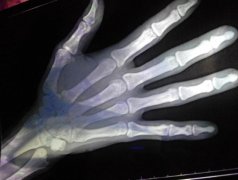

而医生检查发现她侧弯的度数达到了48度,已经到了需要接受矫正手术的程度了,后来医生给她做了脊椎矫形术之后,她的身高增长了7厘米!

也就是说小雪因为这个脊柱侧方,身高足足矮了7厘米!

如果孩子的侧弯已经超过15度了,那么就要去医院治疗,超过45度就需要手术矫正了。